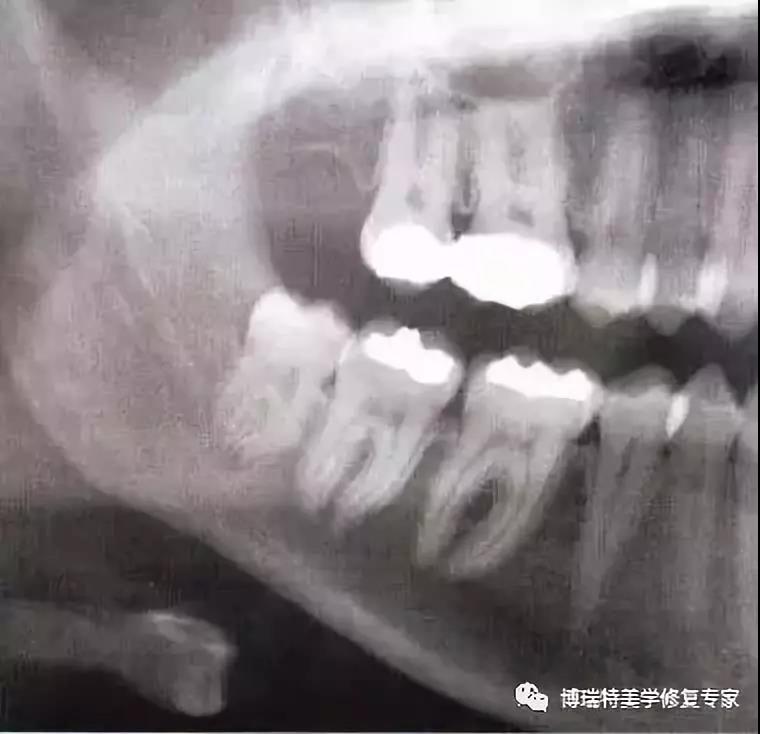

全颌曲面断层×线片,切割牙冠时应经过阻生牙远中面的牙颈部的釉牙骨质交界处。

下颌升支前缘的骨吸收区有利于牙片的取出。

去除颊侧部分骨阻力后,用装在反角机头上的纺锤形车针切割牙冠,用柔韧的小拉钩保护舌侧的黏骨膜。(及舌神经)

该病例也可以不切割牙冠而拔除。拔牙时,去除了牙根间隔。